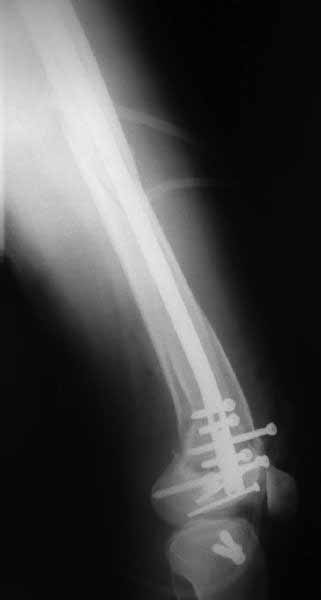

Здесь пример медиальной пластины и латеральный комбинированный метод (у второго больного старый перелом тибиал плато, леченный где то и когда то)

Ответ на эту часть Вашего поста – вложенный файл. Больная оперирована неделю назад по поводу открытого перелома дистального эпиметафиза бедренной кости. После операции она идёт в рентгенкабинет для выполнения послеоперационной контрольной рентгенографии, представленной на слайдах 10 и 11. Узнав, почему её фотографируют, просила передать Вам, Антон, привет.

наружный мыщелок не дорепонироавн - это приводит к вальгусной деформации оси коленного сустава, очень критично для последующей функции.